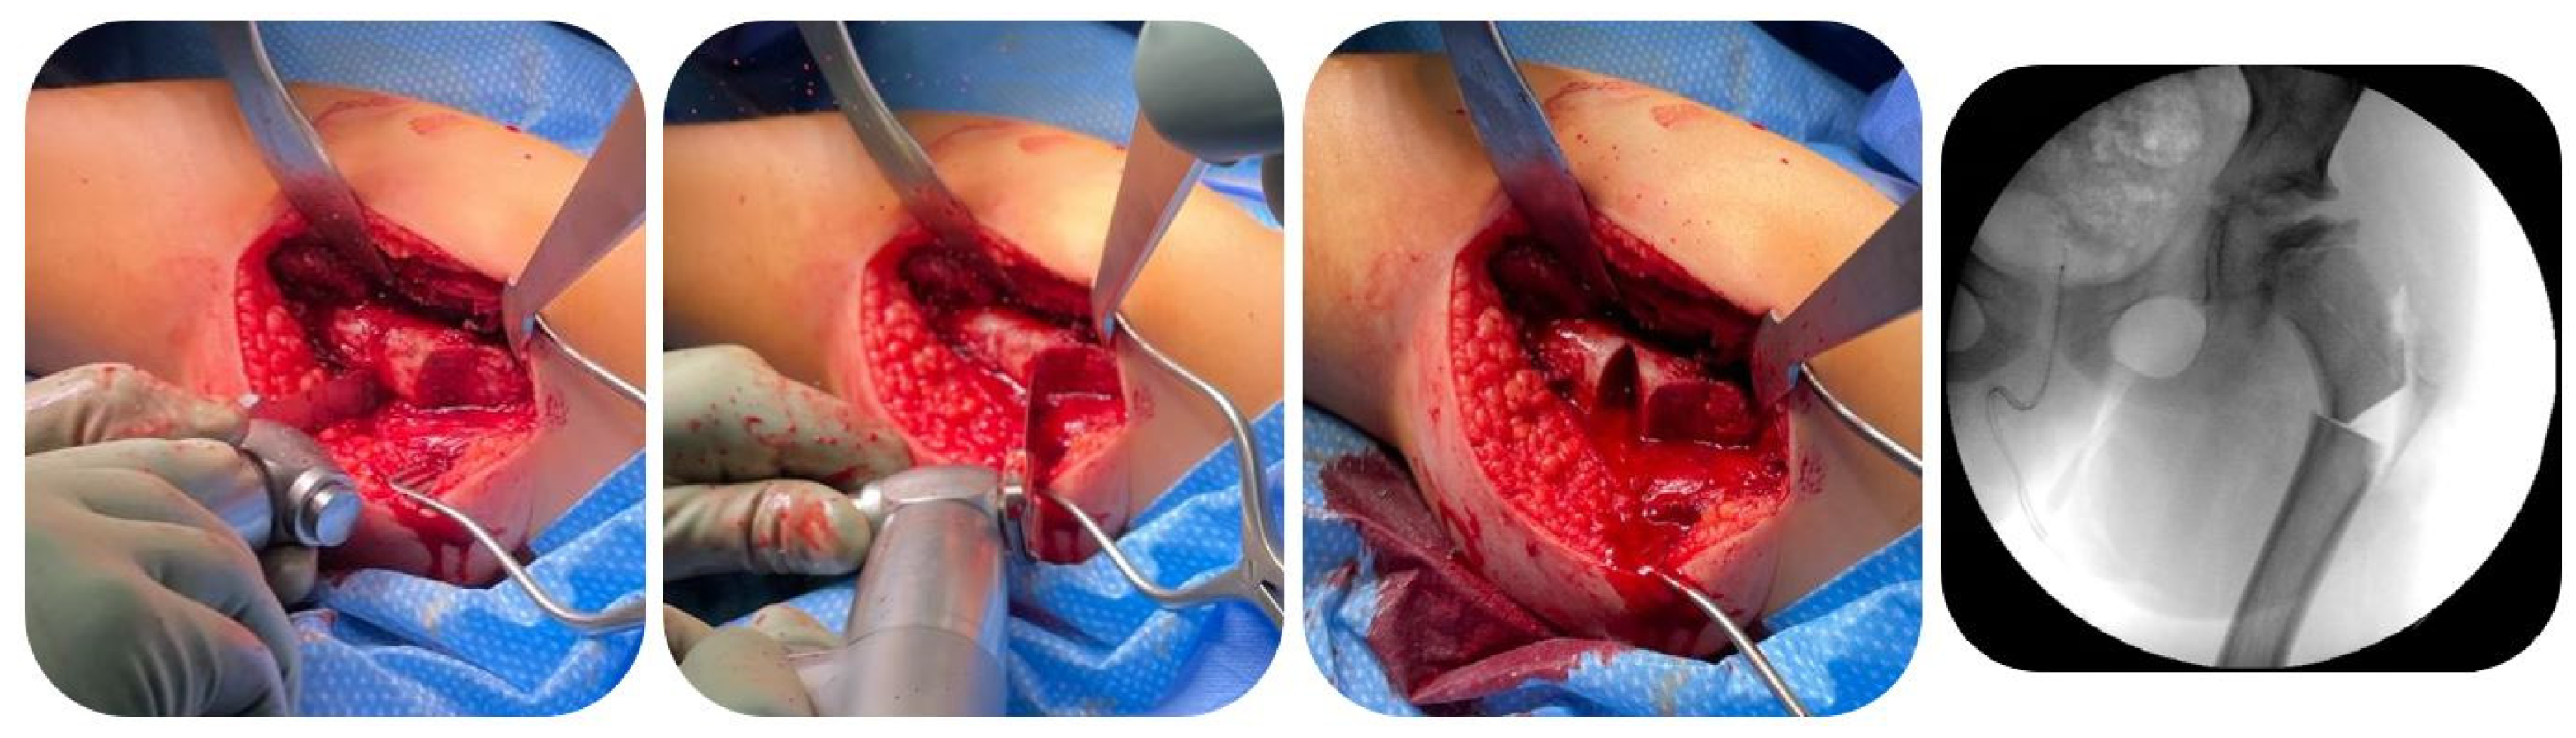

Furthermore, to protect the soft tissues including the medial circumflex artery, subperiosteal retractors were placed circumferentially around the osteotomy site. Subsequently, a recess cut was carried out for medialization of the distal fragment, as the offset of the blade plate was completely filled by the distalized greater trochanter (Figure 3).

Then, the patient was moved to supine position. A guide wire was then introduced into the femoral neck approaching from the distalized greater trochanter under consideration of the preoperatively determined correction angle. After radiographical verification of the correct wire position, the seating chisel and chisel guide were inserted over the guide wire, and the seating chisel was impacted to the appropriate depth (Figure 4a). After removal of the chisel guide, the osteotomy was performed at the proximal femur to achieve the predetermined angular correction, after which the blade plate (90° or 100°; OrthoPediatrics, IN, USA; Figure 4b,c) was inserted over the guide wire. Thus, the blade threaded through the distalized greater trochanter and fixated it to the femoral neck while fixating the plate to the bone in a varus position by locking screws (Figure 4d).

Figure 3. Recess cut at the proximal femur to achieve sufficient medialization of the distal fragment (Patient 3; see Table 1).

Figure 4. After preparation of the implant site with a cannulated chisel (a), a cannulated 90°- or 100°-blade plate is inserted over a guide wire (b,c), threading the distalized greater trochanter and fixating it to the femoral neck (d) (Patient 3; see Table 1).